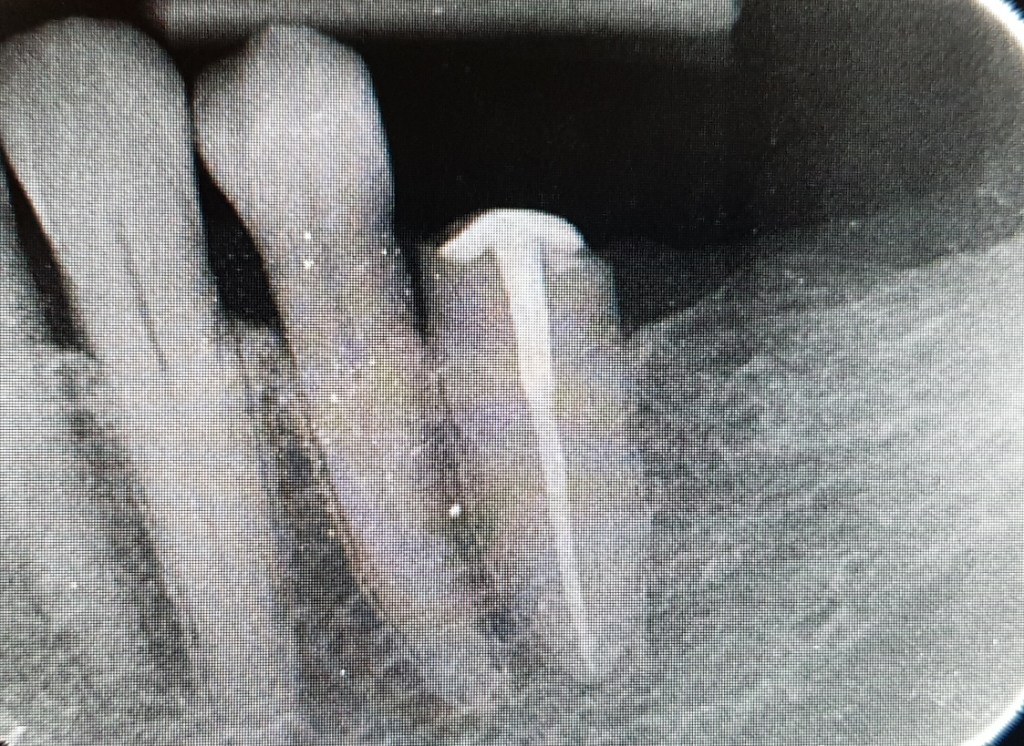

A fenti esetben a páciens nem is reménykedett letört fogának megmentésében és foghúzásra kért időpontot. Mivel azonban a törés, szerencsésen az ínyszint felett történt, gyökérkezeléssel és csapos megerősítéssel a fog megmentése mellett döntöttünk.

A gyökércsatornába beragasztott csap lehetőséget teremtett a fog koronázására, ám statikai okból a szomszédos fogra is korona készült.